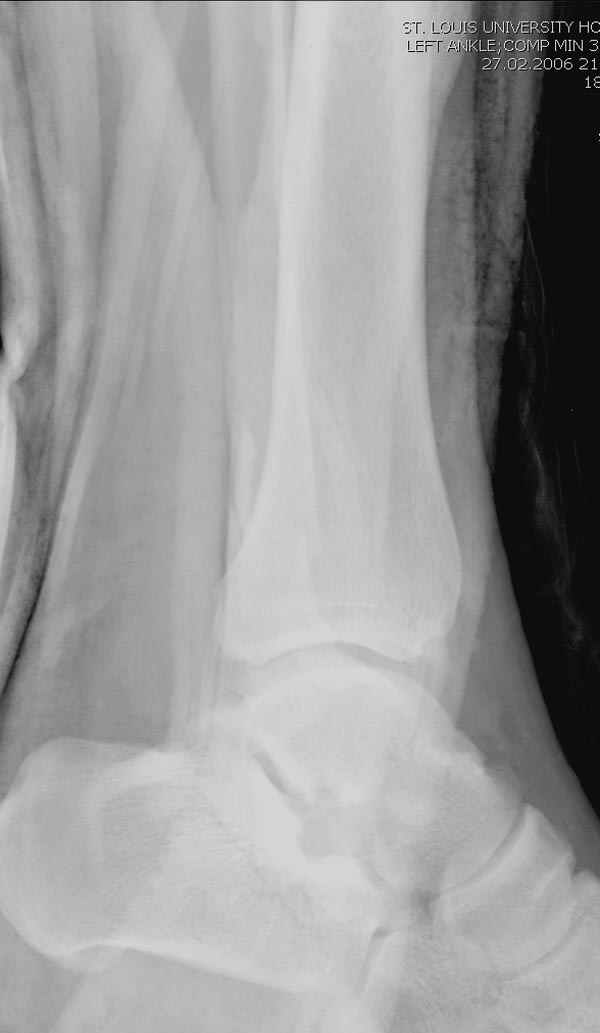

Тему неоднократно разбирали (см. архив), как всегда, недостаточны ренгенологические исследования - кроме прямого и боковых снимков, еще нужна косая ренгенограмма для определения ankle mortise, без мортиз снимка трудно определить высоту и ротацию малоберцовой. (снимки)

Ренгенология даст ответ как классифицировать перелом, на сегодня применяется классификация “Lauge Hansen fracture classification SER supination-external rotation или supination-eversion classification Danis

Weber А, В, С.”

Показания для фиксации: укорочения и ротация малоберцовой, особенно обращают внимание на любой подвывих таранной кости: неустраненый подвывих впоследствии приводит к раннему артрозу. Задний край фиксирует тогда, когда перелом составляет около 25% суставной поверхности голеностопного сочленения и смещение более 2мм.

По снимку ваш случай относится к Weber В, фиксацию производят восстановлением длины малоберцовой кости, под ренгеном (ЭП)контролем, для этого я предпочел бы латеральный доступ, остеотомия по линии перелома, удлинение малоберцовой засчет скоса линии остеотомии, компрессия “lag technique”по линии остеотомии и фиксацию провести латеральной пластиной. Отдельный задний доступ, остеотомия по линии перелома, репозиция и фиксация заднего края вашим предпочтительным методом: 3.5мм шурупом с шайбой или пластиной Antiglide Butress

method. При восстановленном суставе, уменьшится медиальная щель, а при Weber В повреждается только передне-нижняя межберцовая связка синдесмоза, повреждение которой приводит к наружной ротации

малоберцовой, но после восстановления всех смещений, связка автоматический приближается к исходному и нет необходимости восстановления синдесмоза.